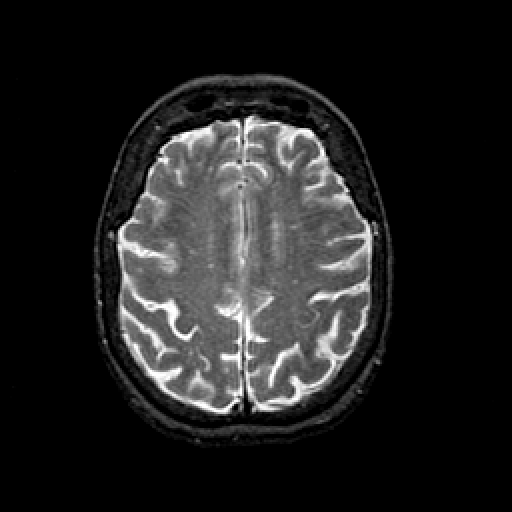

T2-weighted structural MR: Slice 37

Slice 37